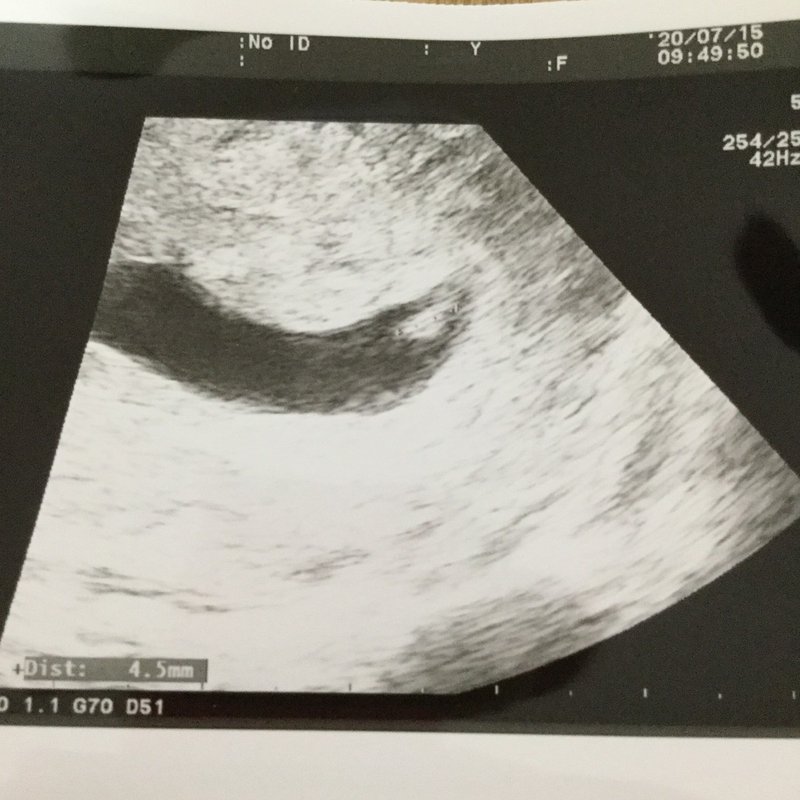

6w1dでは心拍確認できませんでしたが、今日は確認できました。 胎嚢253センチ、 赤ちゃんは37ミリ、 FHR112BPM おなまえ くーのまむ心拍確認できず ケル (Tue) 1902 No 体外受精で妊娠反応がでましたが、6w1dで胎嚢136mmと小さく 心拍確認もできません。 心拍は何週目に確認できましたか? 妊娠初期の妊娠の大まかな目安は8週までに胎児心拍が認められることです。 そのため、 妊娠検薬で早めに妊娠がわかったとしても、 その後心拍確認まで何度も病院に足を運ぶことになります。 およそ1週間ごとに診察

1週間後の今回は6w0dではなく 6w1dの診察指示でした 「6w0dでは心拍確認できない場合があるからね、この1日の差が大事なんだよ」 心拍確認出来なかったと 無駄に不安になる必要はないですもんね いよいよ心拍確認の日です 内診室に呼ばれるまでの間 私の心臓がどうにかなりそうなほど ドキドキしてました (*´Д`*)妊娠週 6w1d 排卵日が特定できているので、確実に6w1dのエコーです (^^)元気な心拍と2mmの赤ちゃんが確認できました! 2人目の妊娠なので、まだ1歳10ヶ月の長男を抱っこしたり追いかけ回したりでゆっくりできないので、赤ちゃんが心配ですが生命力を信じて

心拍は最低どのくらいまでに確認できないといけないのでしょうか? ・8/6 計算上6w1d GS=92mm ・8/ 〃8w1d GS=25mm ・8/27 〃9w1d GS=219mm 補足:もともと生理はほぼ28周期で安定、1人目は3年子供ができず不妊治療(体外受精)にて出産、その際採卵後の卵がなかなか心拍確認ができる週数の目安はおおむね 6w~7w といわれています。 一般的に6wで確認できなくても問題にはならず、7w台で確認できないと心配なようです。 私の場合、5w1dで無事胎嚢は確認できたものの、着床が遅れたのが原因で週数にしては小さめの結果でした。妊娠週 6w1d 6wに入ってすぐ、つわりが出始めました。 卵黄嚢と胎芽がみえ、拡大してもらうと心拍も確認できました。 次回は二週間後、成長が楽しみです。 里帰り出産のため、里帰り先の産婦人科に電話しました。 人気のある病院はすぐに埋まって

6週で心拍が見えるなんて順調ですね、と言っていただけました。 心拍が見えたのでやっと安心できます。 心拍確認ができれば流産の確率はぐっと下がる、って言いますよね。 エコー写真と分娩予約の紙などをもらい、診察終了。 次回は3週間後です。 (参考)1日前のの6w1dでの心拍確認済みの割合は、75%でした。 6w1d心拍確認できない割合、胎嚢・胎芽の平均的な大きさを調査 今回調査した50名の妊婦の内訳は、出産が44名、流産が6名でした。 出産できた44名のうち、6w2dで心拍確認できたのは28名です。About Press Copyright Contact us Creators Advertise Developers Terms Privacy Policy & Safety How works Test new features Press Copyright Contact us Creators